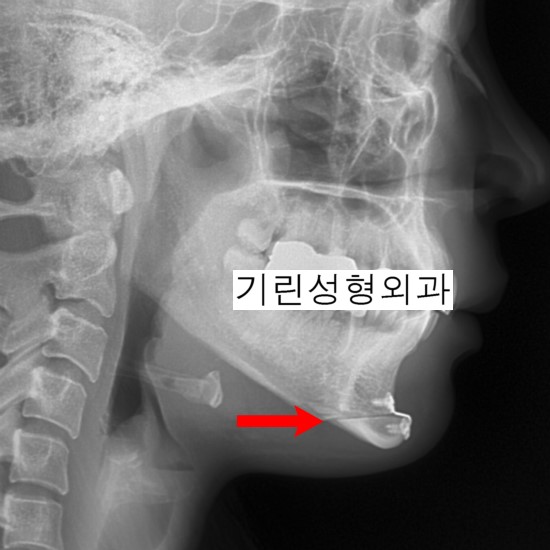

아래는 앞턱수술 전과 후의 엑스레이입니다. 수술은 앞턱을 T모양으로 자른 뒤 중앙으로 모아주거나 앞뒤로 이동시키는 방법으로 진행됩니다. 무턱인 경우 잘라낸 앞턱을 앞으로 빼주는 방법으로 진행되며 경미한 주걱턱인 경우 잘라낸 앞턱조각을 뒤로 넣어주고 고정합니다.

턱이 길어 길이를 줄일 필요가 있는 경우에는 길이조절이 가능한 수술방법입니다.

앞턱전진 전

앞턱전진 후

위 사례는 앞턱과 사각턱수술을 병행한 것으로 귀밑각이 없고 앞턱만 넓고 긴 경우 미니브이라인수술인 티절골을 통해 갸름한 라인이 가능합니다.